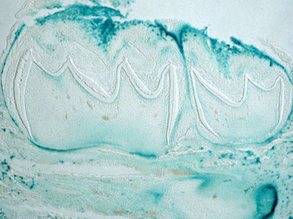

Spine Tingling

Born on this Day